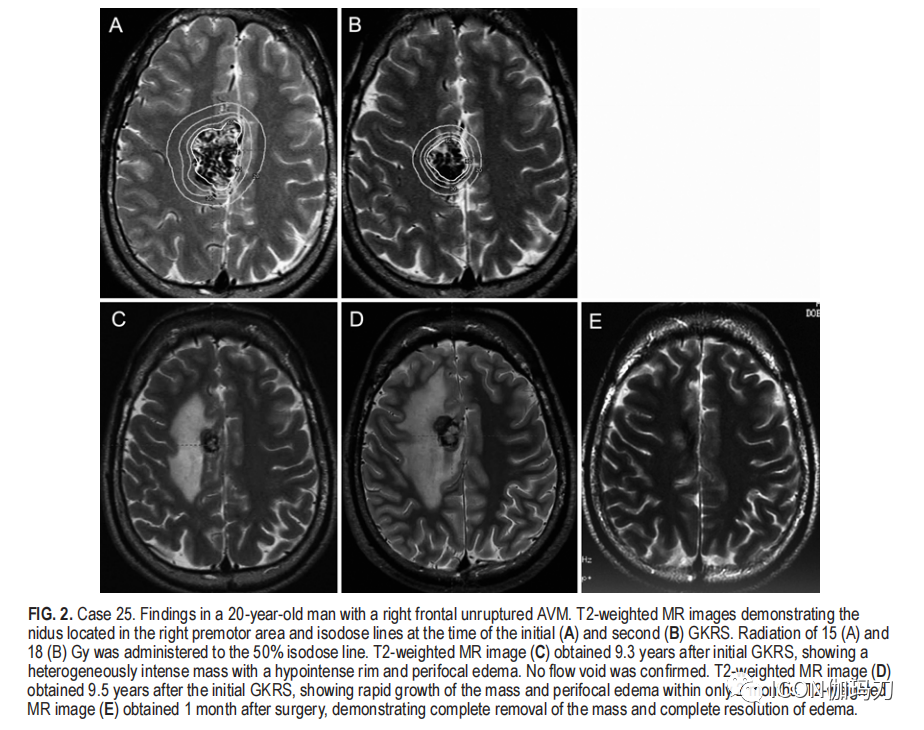

病例25

20岁男性,全身强直性惊厥。MRI和DSA显示右侧额叶有动静脉畸形。该患者在首次治疗后6年再次进行GKRS检查残余畸形血管巢。在第一次GKRS治疗的9年后,MRI偶然发现了一个类似海绵状血管畸形的小肿块。患者最初无症状,但2个月后出现明显左侧运动无力,肿块增大,灶周脑水肿(图2C和D)。术前检查证实畸形血管巢完全闭塞,手术切除肿块。术后不久,脑水肿和运动无力消失(图2E)。组织学显示RFEH伴血肿毗邻变性血管,与变性畸形血管巢相吻合( Histology showed RFEH with the hematoma adjacent to the degenerated vessels, compatible with a degenerated nidus)(图4)。

2。病例25。一例20岁男性右额部未破裂动静脉畸形。T2加权MR图像显示病灶位于右侧运动前区,首次GKRS 治疗(A)和第二次GKRS 治疗(B)时的等剂量线。对50%等剂量线给予15Gy (A)和18 Gy(B) 的照射。初次GKRS治疗后9.3年获得的T2加权MR图像(C)显示一个非均匀信号的肿块,边缘低信号和焦周脑水肿。确认无流空。初次GKRS治疗后9.5年获得T2加权MR图像(D),仅在2个月内肿块快速增长和焦周脑水肿。术后1个月获得T2加权MR图像(E),显示完全清除肿块,水肿完全消退。